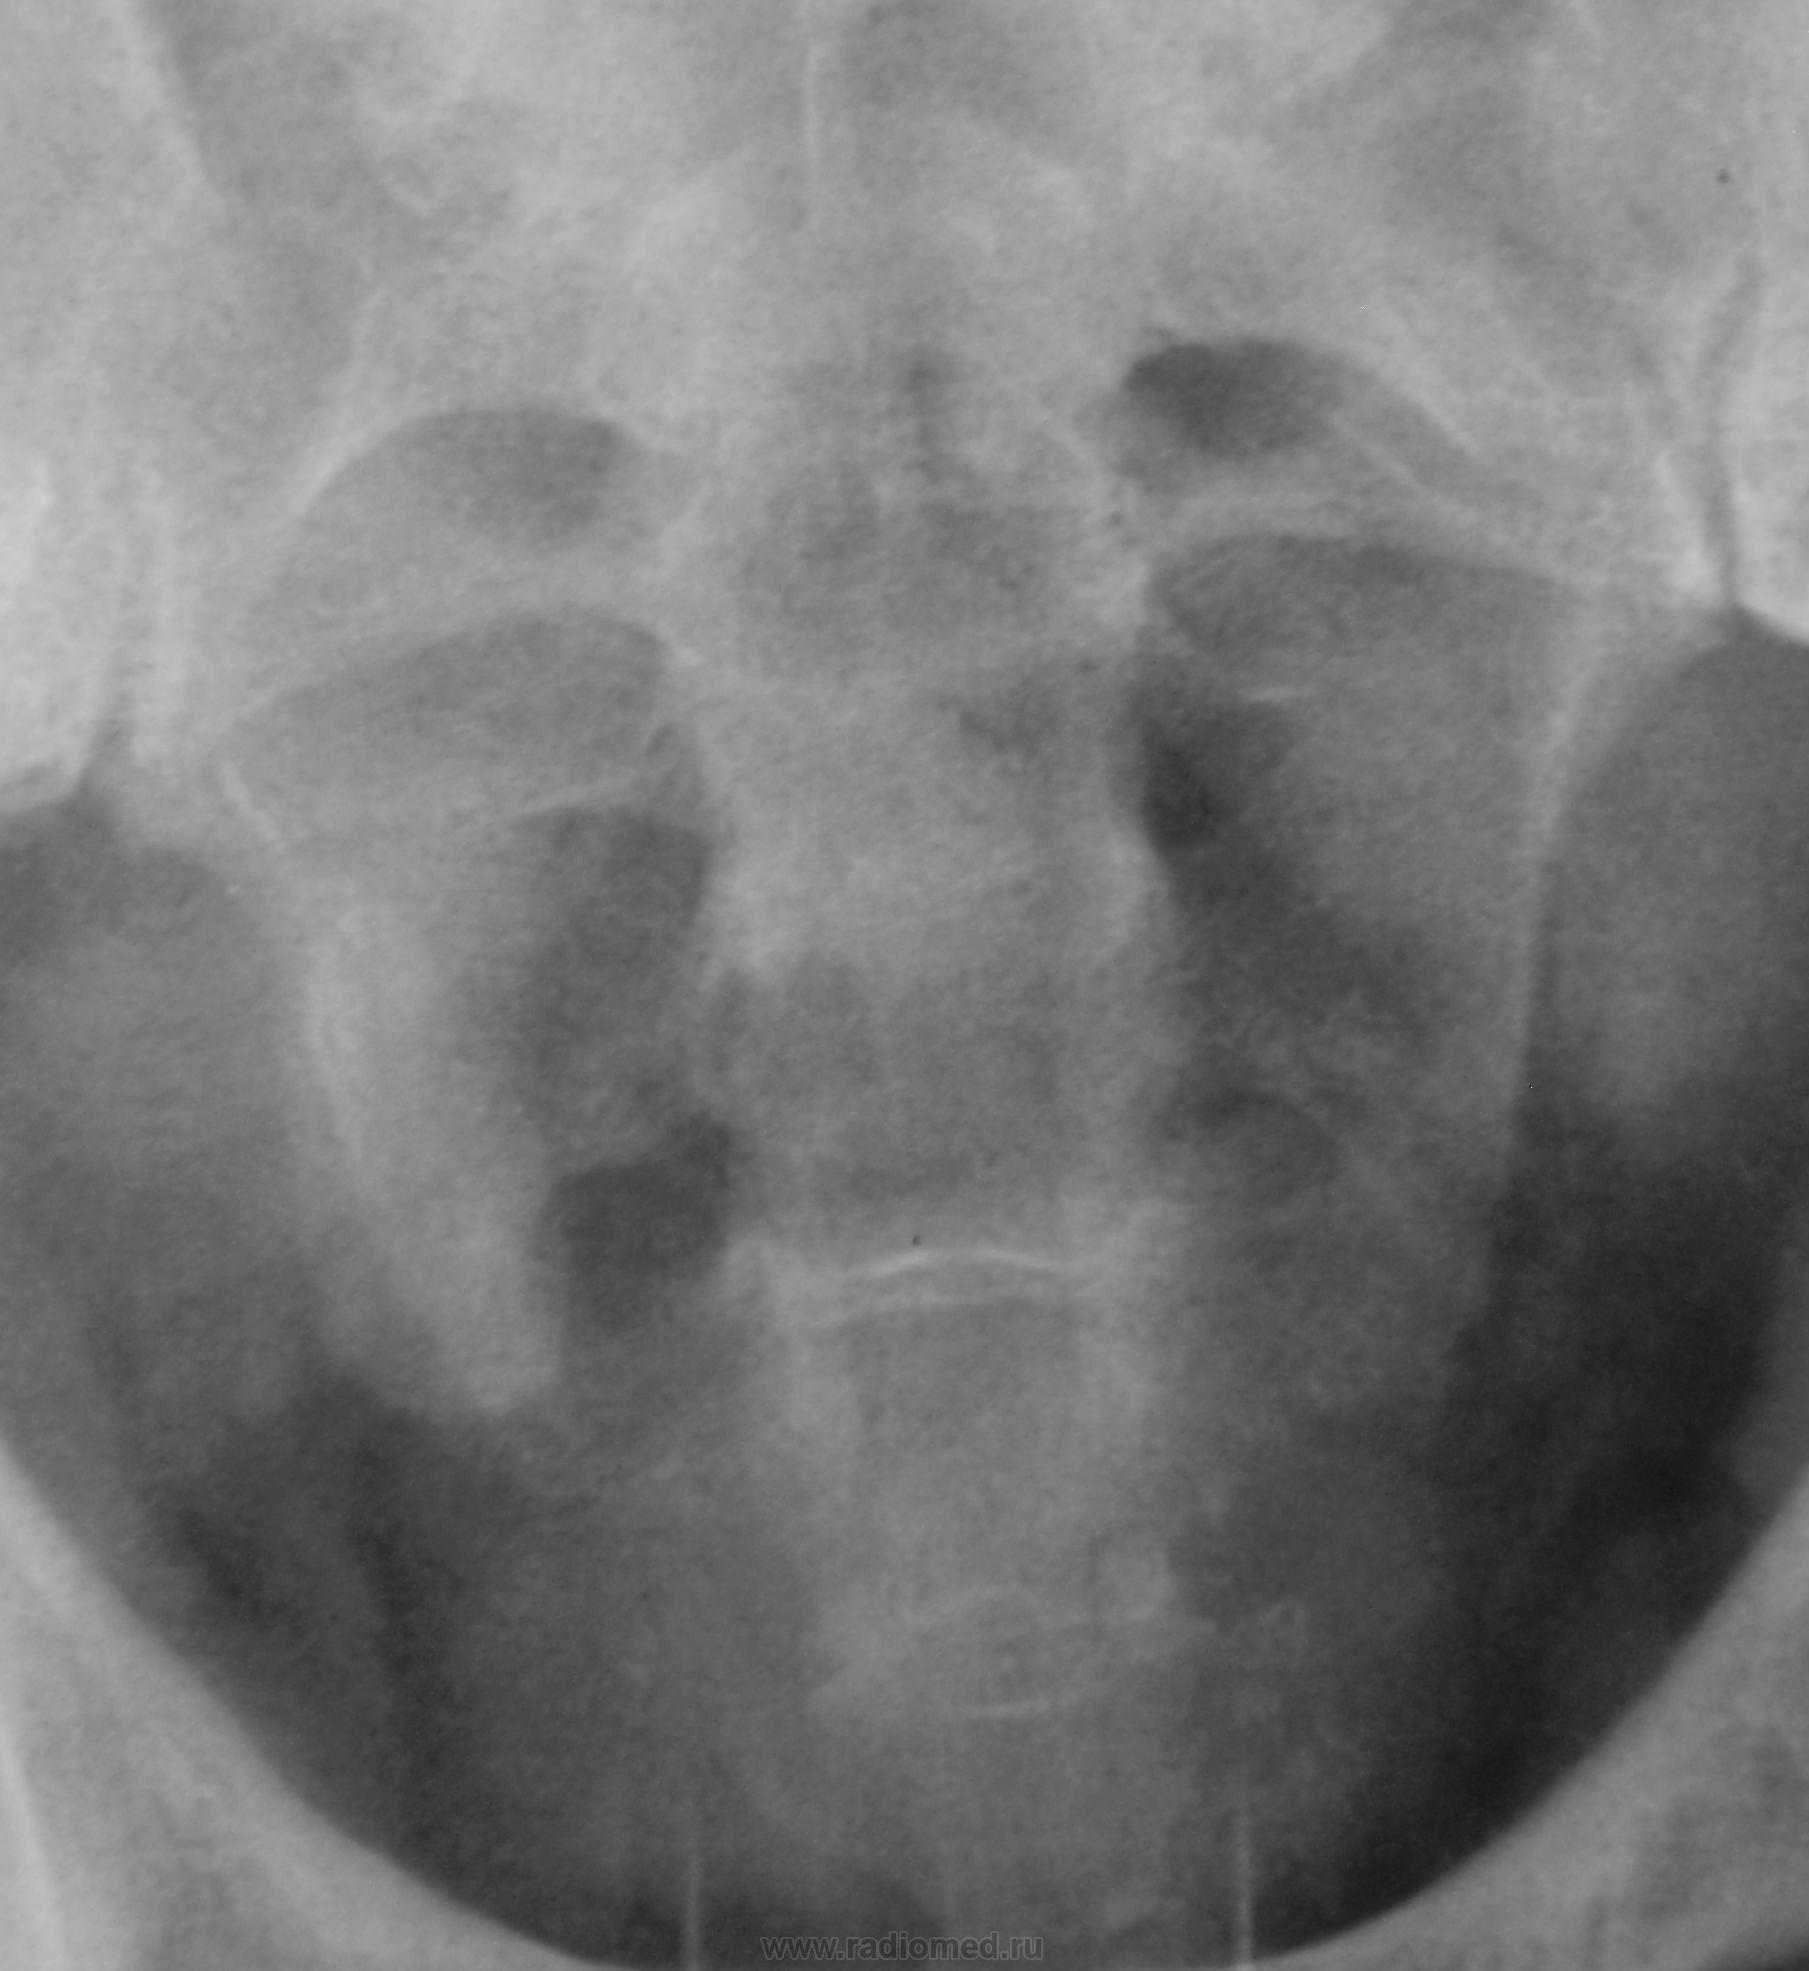

Пациент с диагнозом "МКБ" направлен на обзорную рентгенографию почек и мочевыводящих путей.

Пациент с диагнозом "МКБ" направлен на обзорную рентгенографию

Внутривенная урография.

Да с камнем желчного то все понятно...но вот тень в проекции н\трети правого мочеточника ....весьма необычна...вопрос - куда ее "пристроить"?))))

Я не про "утверждаю", Боже спаси, для мочеточника тень очень больших размеров, хотя расположена вдоль его проекционной оси, но здесь же проекция крупных сосудов, стенты сейчас могут быть всякими разными, а потом-в малом тазу не только у женщин, но и мужчин хватает всякого, что может обызвествляться. А верхняя тень-типично для желчного пузыря.

Да, камешек для желчного типичный.

А тень в дистальной трети мочеточника действительно "фердиперсовая"...

Признавайтесь, куда делась средняя треть правого мочеточника? Ее как-будто ножом отрезали под линейку, а ниже-сплошное безобразие! "ЧТО" может как обезобразить орган-банальная МКБ с частичной обтурацией просвета или опухоль? А в пузыре тоже камни?

Вы правы, камней не много, их - до "фига"...

Отчего же не смущает?))) смущает...она и есть первопричиной образования ТАКОГО камня в мочеточнике, теперь об этом можно сказать с уверенностью, ее генез - выраженое увеличение размеров простаты.